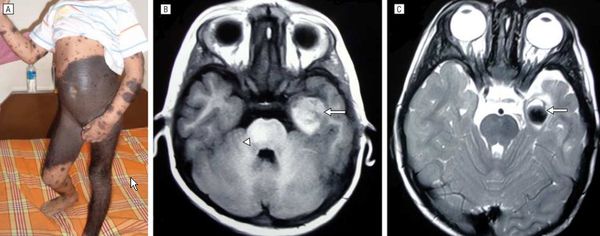

а - Меланоз токсический ретикулярный у пациента 50 лет.

б - Крупный план очагов поражения.

В 45 лет появились гиперпигментированные пятна на коже лобно-височных областей, которые постепенно распространились на кожу лица и шеи. Пациент в течение 11 лет участвовал в заправке топливом военных самолетов; неоднократно, но без эффекта лечился амбулаторно и стационарно. Диагноз «меланоз токсический ретикулярный» был впервые установлен в возрасте 50 лет в кожно-венерологическом отделении госпиталя на основании клинико-анамнестических данных и результатов гистологического исследования. Гистология — в срезах кожный фрагмент с несколько атрофичным эпидермисом, умеренным гиперкератозом и акантозом. В верхних слоях дермы очаговая инфильтрация преимущественно лимфоцитами и очаги скопления меланина.

Придатки кожи не изменены. Морфологическая картина соответствует меланодермии. Лечение — витаминотерапия (С, В1, В6, В12, в/м, № 10 каждого витамина), плазмаферез (4 процедуры), наружное применение 20% крема «Скинорен» 2 раза в день.